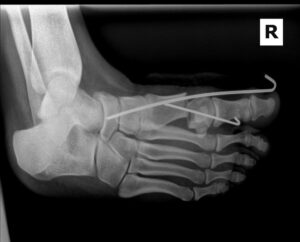

Minimal incision bunion surgery is a modern technique designed to correct bunions using small incisions. Unlike traditional open surgery, which requires a larger incision and more soft tissue disruption, MIS allows surgeons to realign the bones and soft tissues through tiny cuts.

This technique uses specialized instruments and imaging, such as X-rays, to ensure precise correction of the deformity while minimizing trauma to the surrounding tissues.